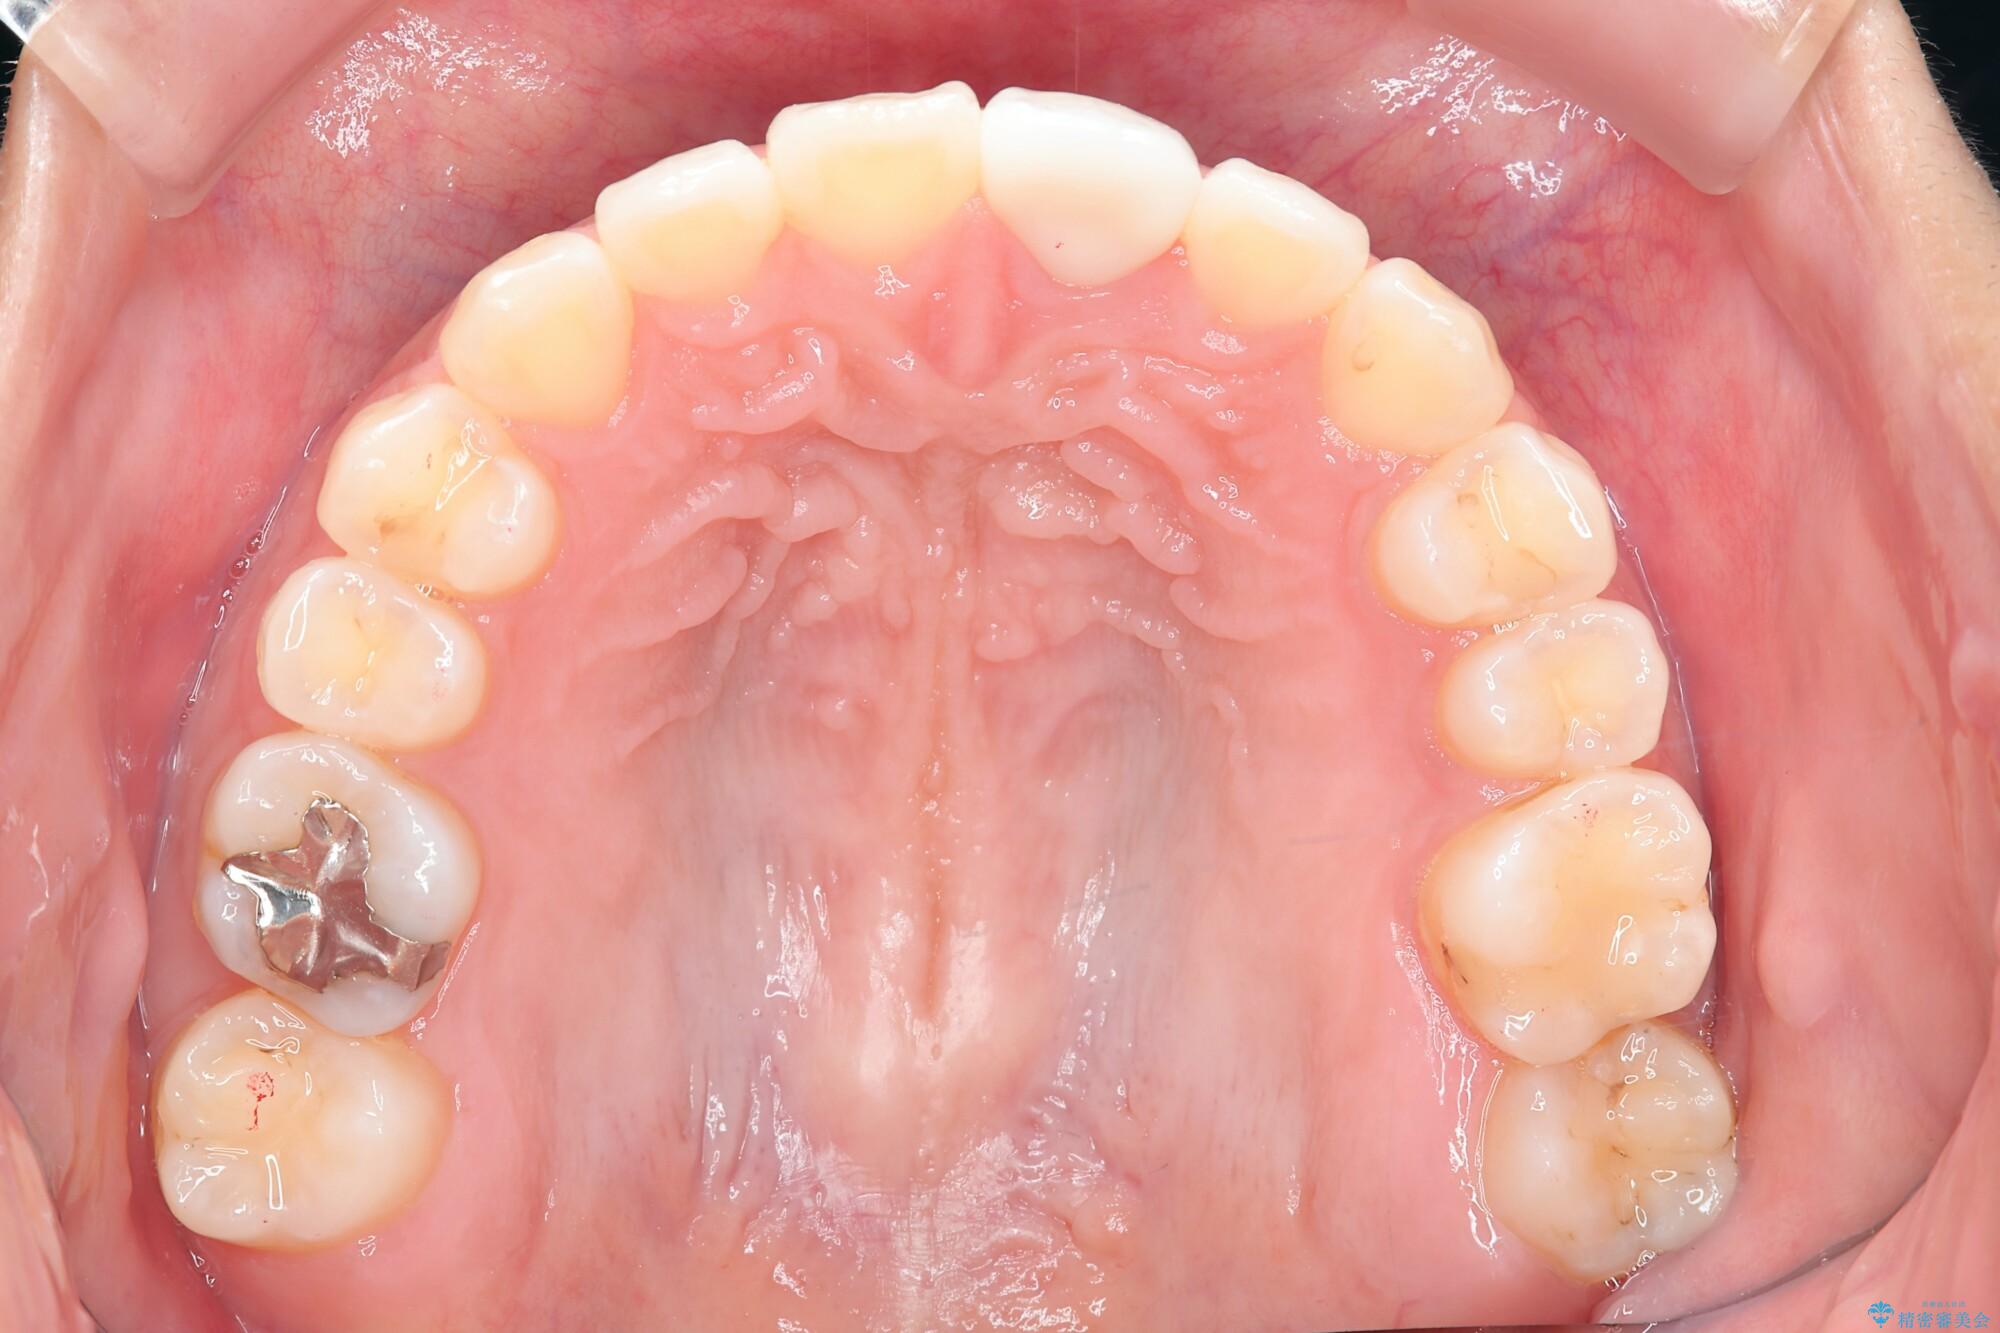

仕上がりにこだわりたいと、装置はマウスピースではなくワイヤーを希望されました。

マルチブラケットを用いた非抜歯のワイヤー矯正で噛み合わせと歯並びを改善していきます。

1年で歯並び、嚙み合わせともにしっかりと改善されました。

患者様にも、非常に噛みやすくなったと喜んでいただくことができました。